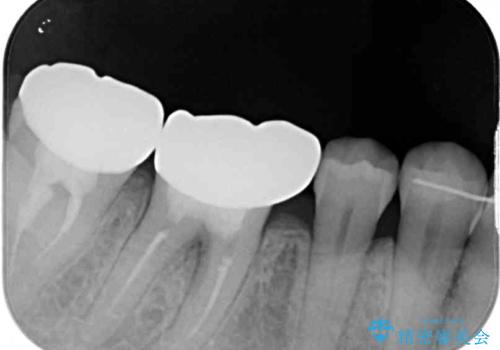

- 前歯の隙間と奥歯の目立つ銀歯を気にして来院された患者様です。

インビザラインにより下顎前歯の隙間を閉じるとともに、奥歯の咬み合わせを改善させることとしました。

矯正治療後には、銀歯のクラウンをセラミッククラウンへ替える補綴治療を行うこととしました。

左右奥歯の咬み合わせを変更させる必要があったため、治療期間は長くなることが予想されました。